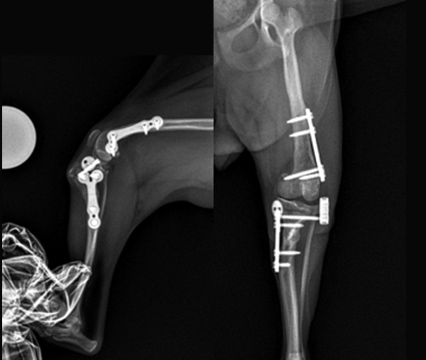

슬개골 탈구 내측 4기, 십자인대 질환

- Case: DFO + TPLO + TTT 수술

- 9살 9.5kg 시바이누

현증인 십자인대 질환에만 집중할 경우 십자인대 질환에 대한 교정 수술인 TPLO만 진행할 수 있습니다.

현재, 슬개골탈구 교정이 같이 필요한 환자의 경우 DFO 수술을 같이 하고 있습니다.

이럴 경우 환자의 보행이 현저하게 개선이 되고 다시 마음껏 뛰어다닐 수 있습니다.

DFO: Distal Femoral Osteotomy, 대퇴골 골기형을 교정하는 수술